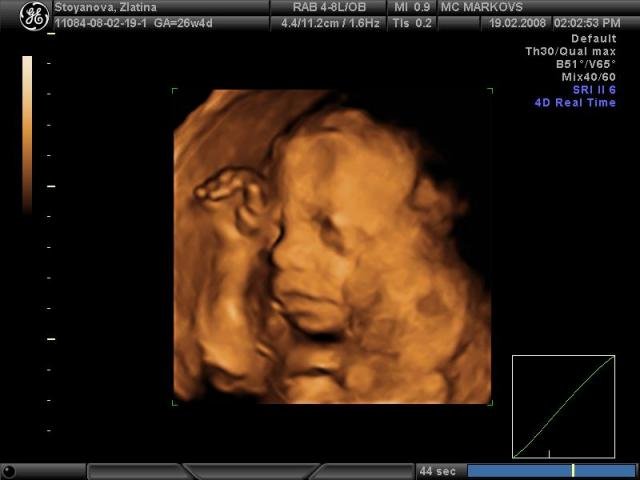

Госпожица е,  вече има и доказателства, ама не и на хартия! за сега е 850г в 26 седмица, което било добре!